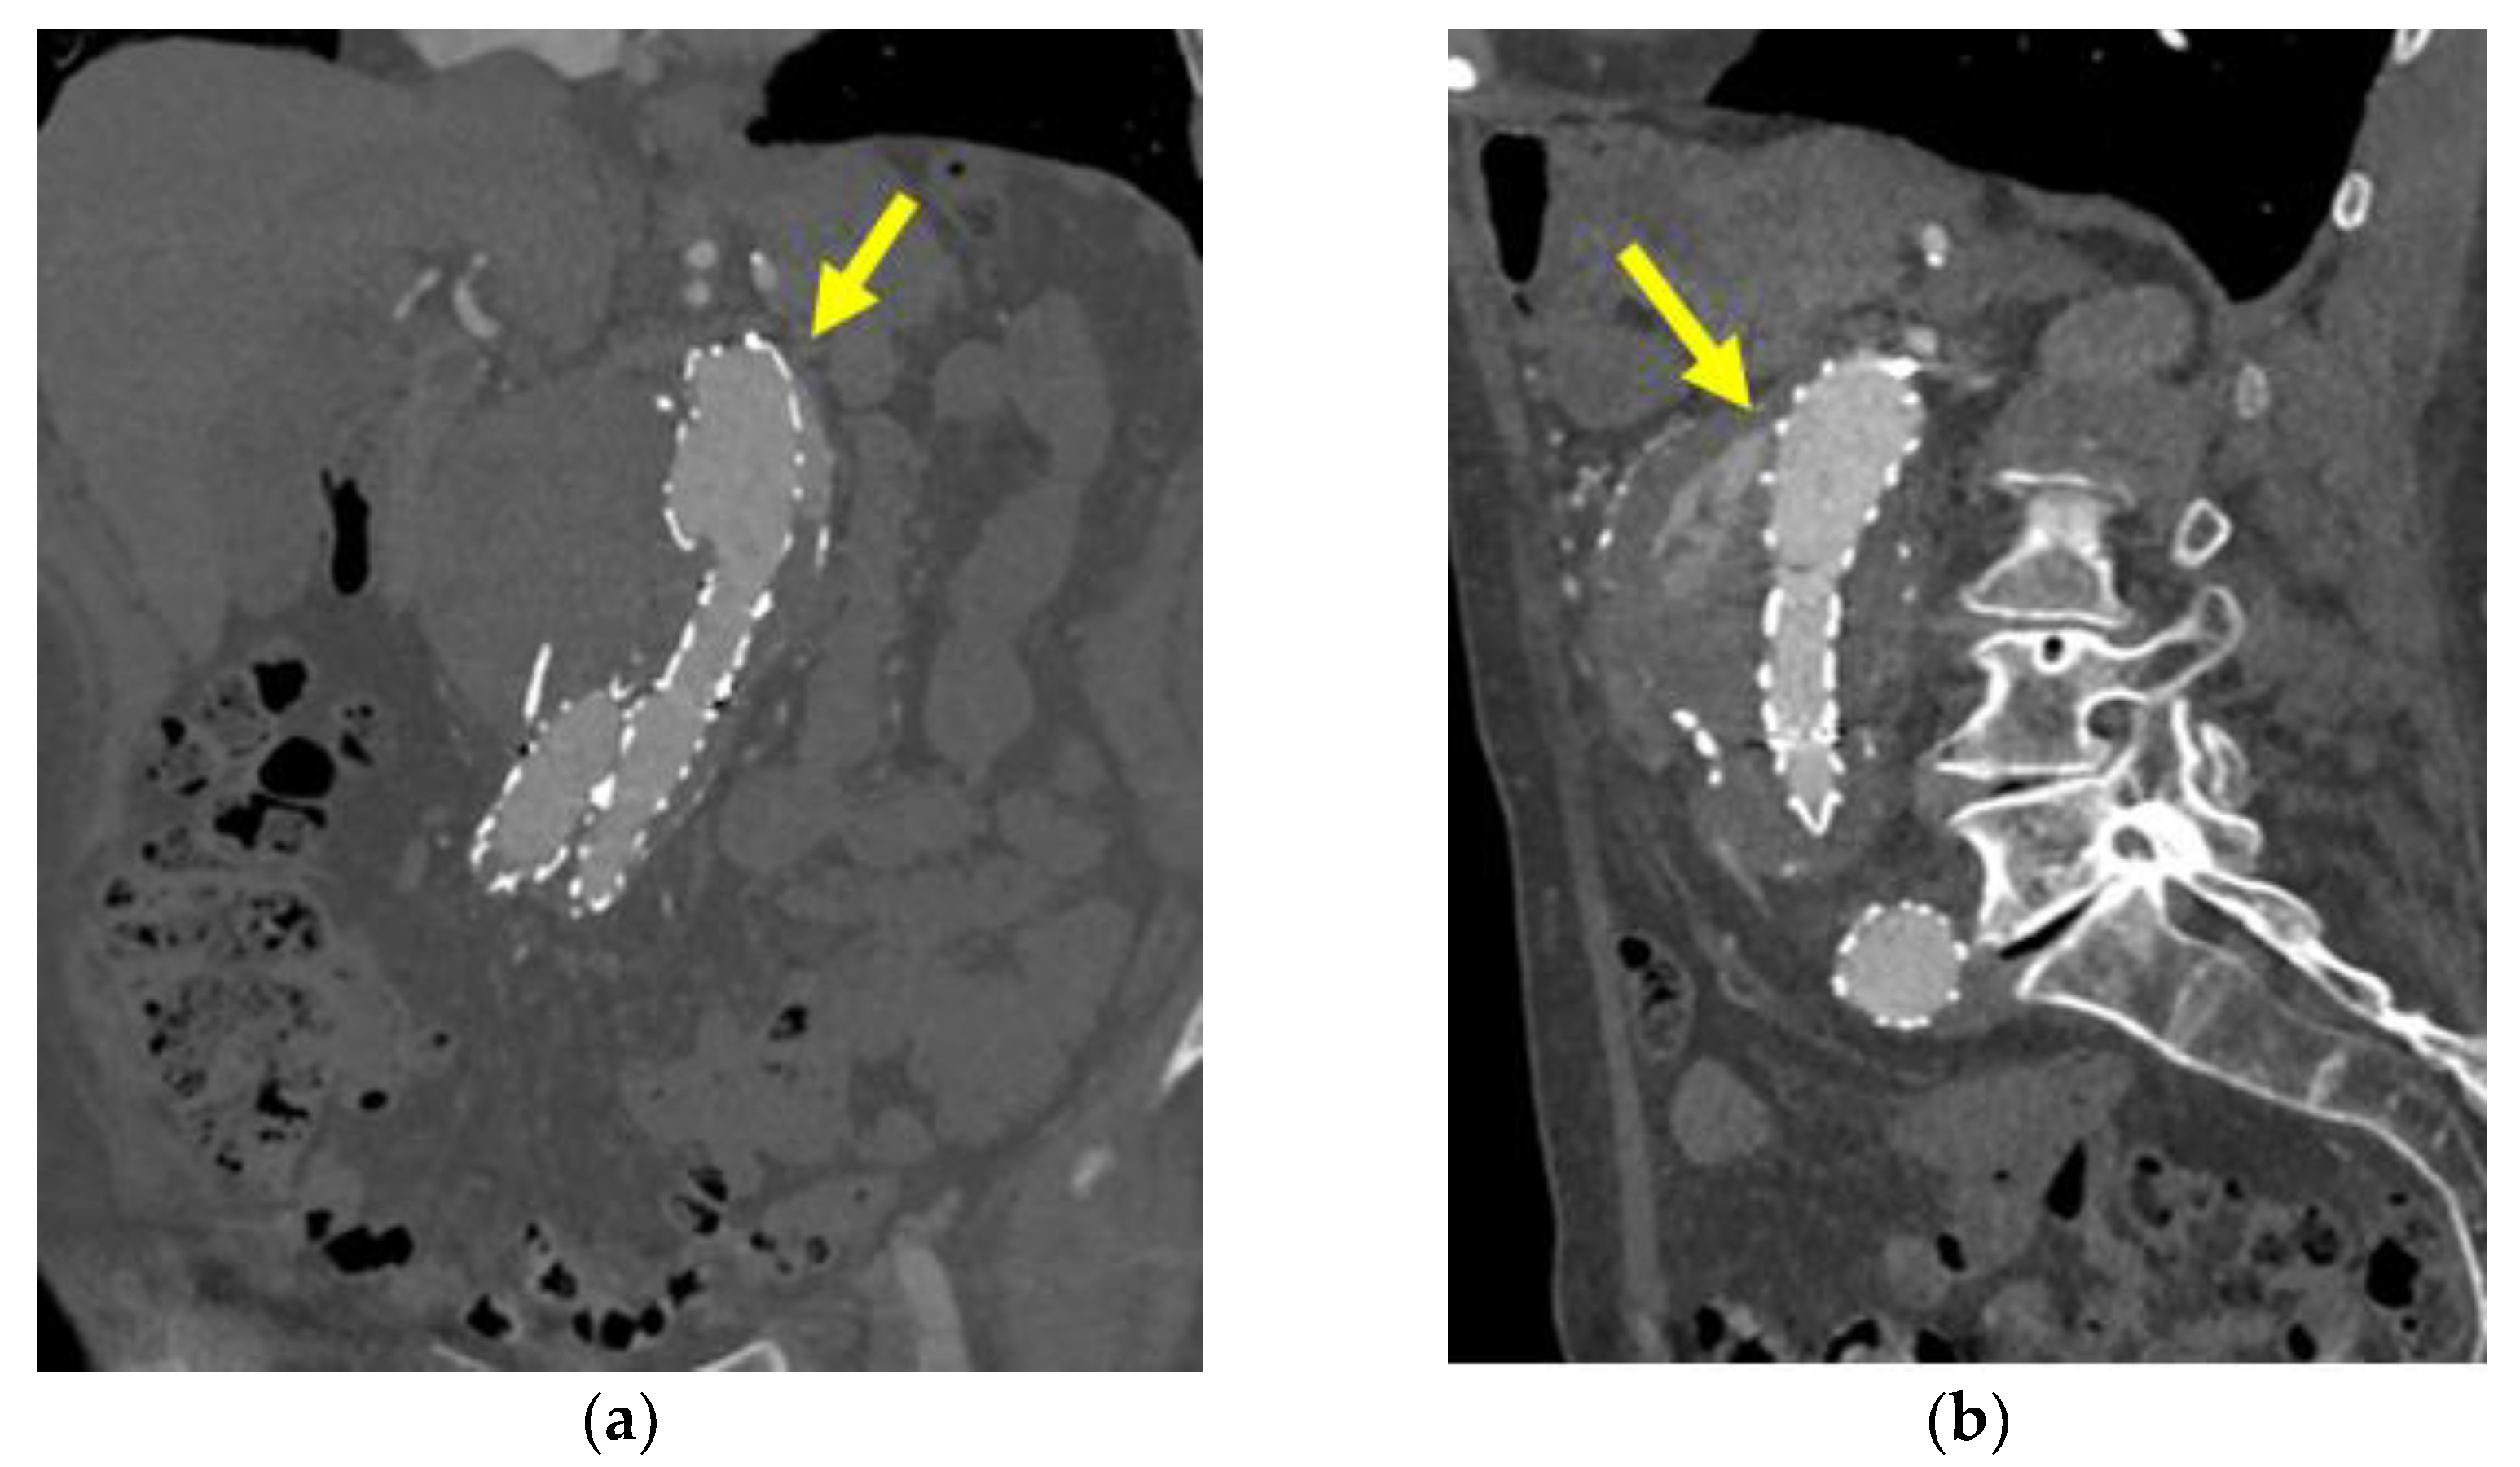

3.3. Embolization of ELIA

4. Discussion